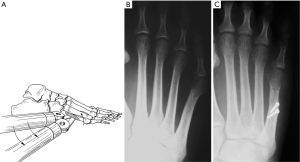

Symptomatic bunionette deformities have been associated with anatomic variants. Coughlin previously described several anatomic factors that may contribute to the painful condition. These include prominence of the metatarsal head, congenital plantarflexed or dorsiflexed metatarsals, increased four to five intermetatarsal angle (IMA), and lateral bowing of the metatarsal shaft (1,2). These variants led to the creation of a classification system which will be discussed later. Typically the toe is adducted compared to the metatarsal (Figure 1). Other congenital deformities such as splayfoot and brachymetatarsia have been linked to development of bunionette deformities (3,4). Soft tissue abnormalities may accompany bunionette deformities (3,4). Plantarflexed metatarsals, ankle and hindfoot deformities are associated with plantar callosity and increased pressure against shoe wear (5).

Radiographic evaluation begins with standard weight-bearing radiographs with anterior posterior and lateral views. Several angles have been described in the assessment of bunionette deformity. Most commonly, the 5th MTP joint angle (MTP-5 angle), the 4–5 IMA and the fifth metatarsal lateral deviation angle are calculated (Figure 3). Average MTP-5 angle is 10.2, while 90% of normal feet have an angle of 14 degrees or less (14).